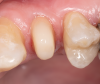

Fig 2. Restorative failure of an existing amalgam restoration on the maxillary left first premolar from recurrent caries.

Figure 2

Restorative failure of an existing amalgam restoration on the maxillary left first premolar from recurrent caries is documented here (Figure 2). The periapical radiograph revealed an extensive carious lesion extending into the pulp chamber. After clinical and radiographic evaluation, a treatment plan was discussed with the patient that included endodontic therapy, crown lengthening, and reinforcing the root and supporting the tooth-restorative complex with a fiber-reinforced post and core system.